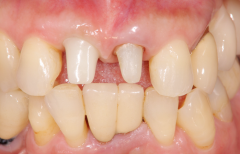

先欠(生まれつき歯がない)状態を矯正治療とインプラントで治療した症例

矯正で歯列を整え、先欠部にインプラントを埋入しセラミックの歯を入れて仕上げたケース。

約20年経過後も問題はございません。